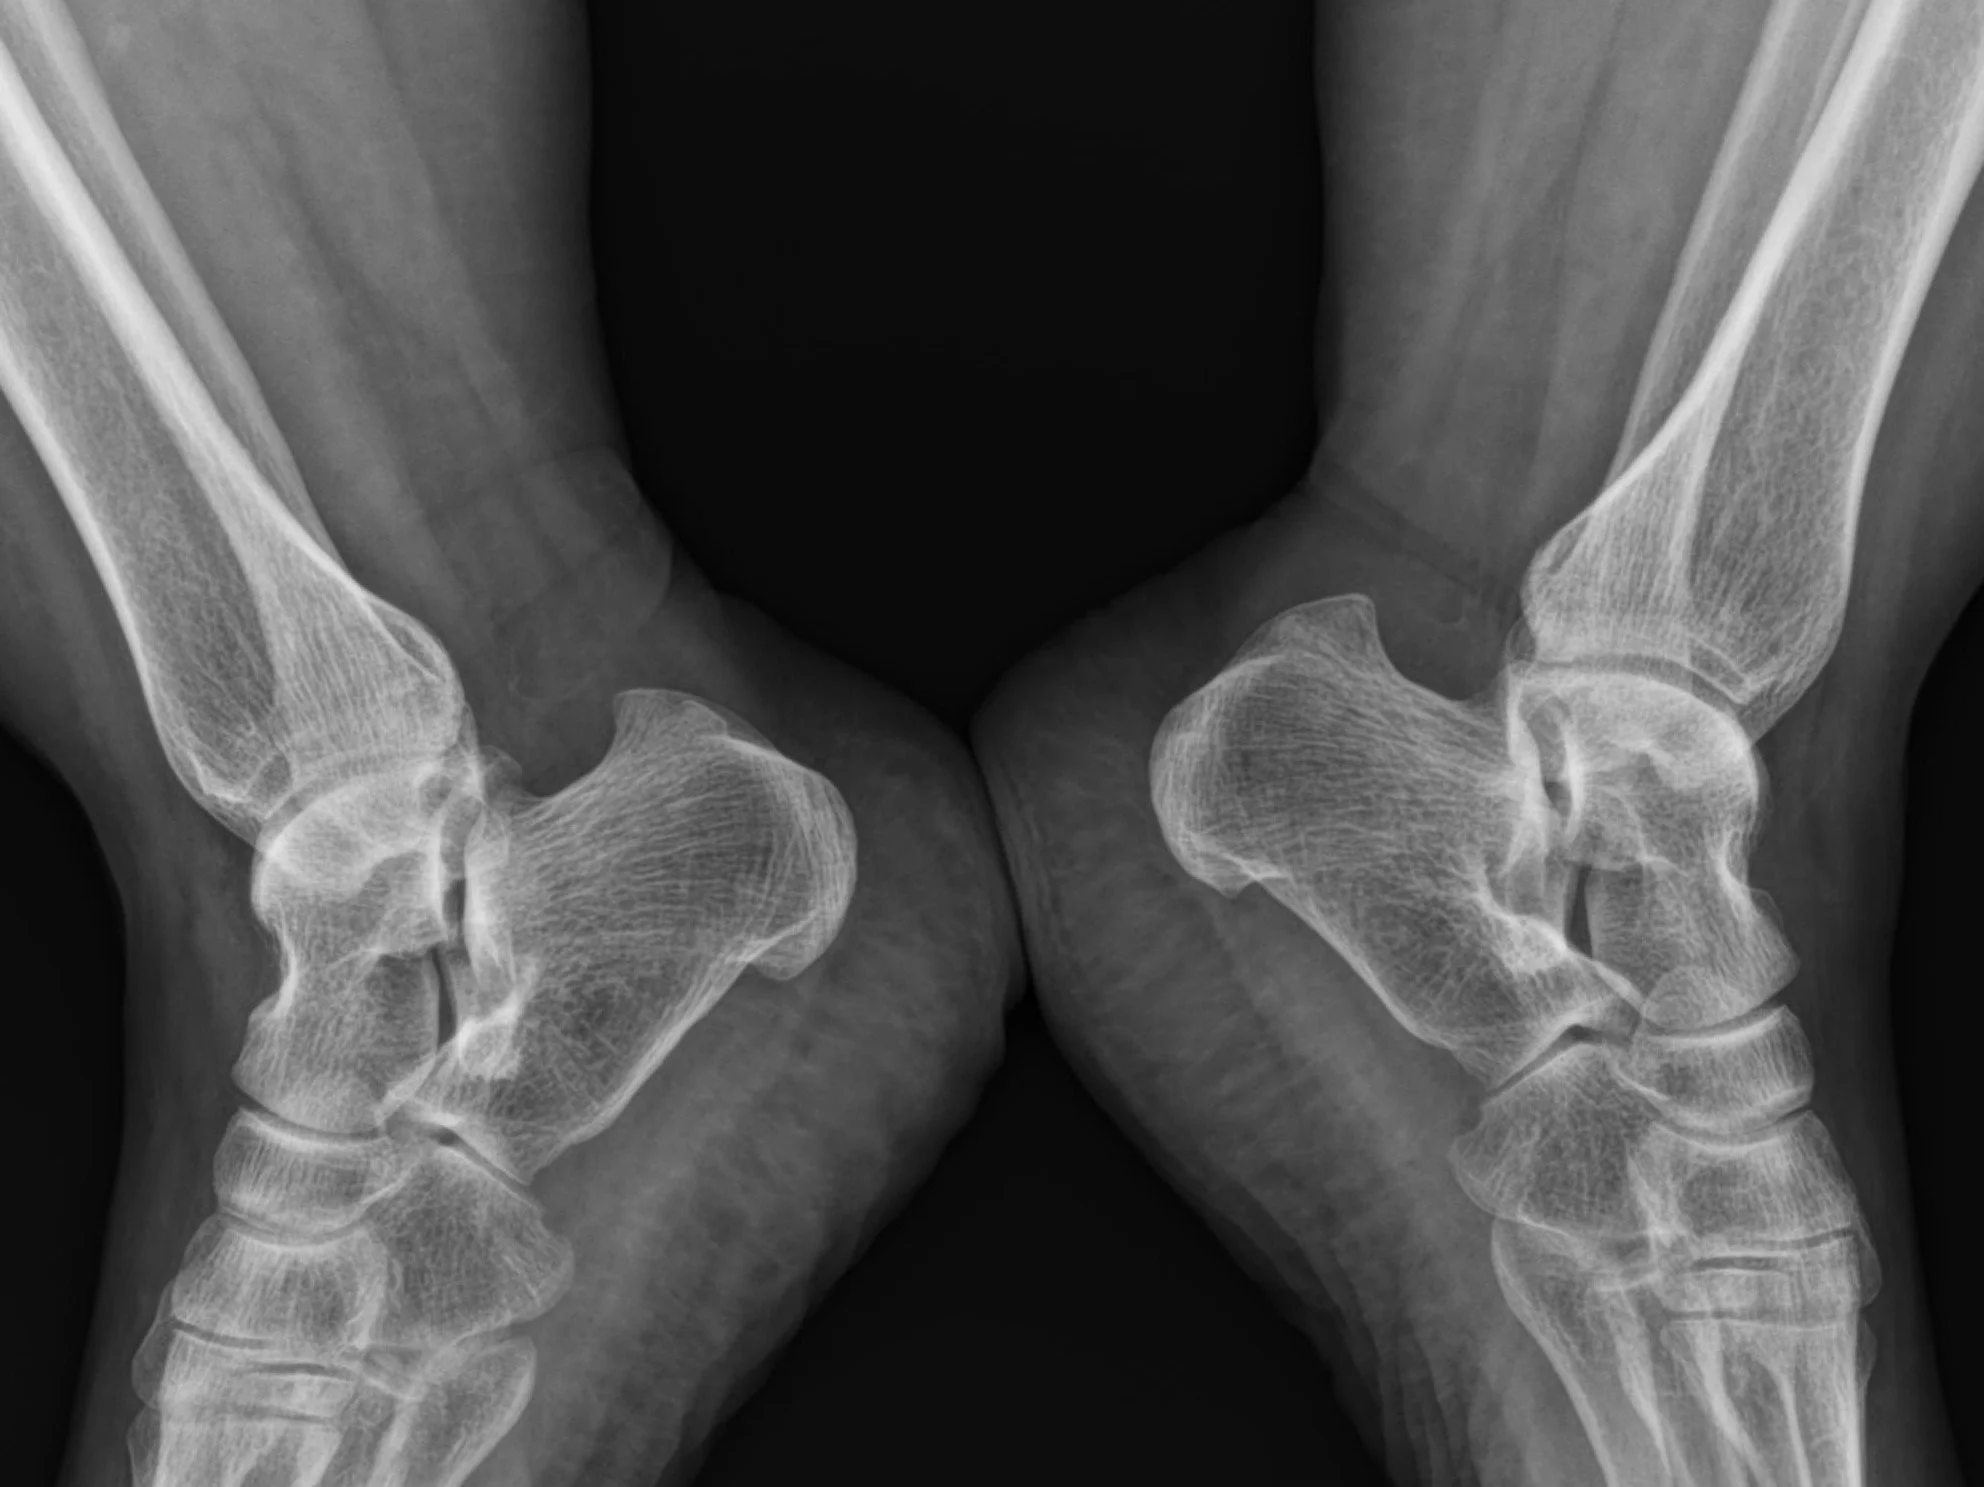

Haglund Deformity

• Bony enlargement formed at the posterosuperior aspect of the calcaneous.

• Can lead to retrocalcaneal bursitis.

• Associated with repetitive trauma and tight shoes.

Case courtesy of Mohammad Taghi Niknejad, Radiopaedia.org, rID: 93348 (Haglund deformity)